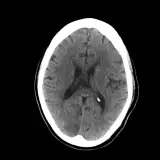

Over 2,100 interactive radiology cases, curated by radiologists for your level of training. Scroll, window, and view cases full screen โ€” just like on PACS. Click linked findings in each writeup to jump straight to them on the image. Cases include sample reports, a focused discussion section, original illustrations, and videos.

Our site includes 3 main courses: Call Preparation, Introduction to Radiology, and Neuro Fellowship.

Neuro Fellowship โ€” a course tailored for fellows and practicing radiologists with in-depth reviews of advanced neuro topics like brain tumors, featuring rare diagnoses, differentials, and clinical pearls.